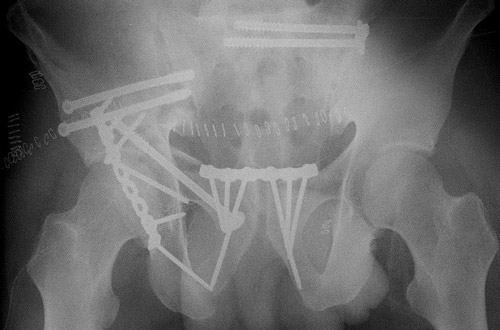

Pre-op X-Rays after applying correct amount of binder compression

Pre-op X-Rays